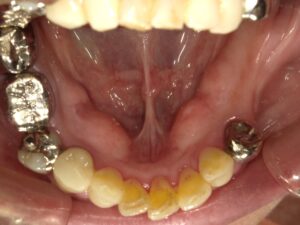

コーヌスデンチャーとは残っている歯に冠のような金属を被せてその上にさらに金属を被せる

2重の冠でできた入れ歯になります。茶筒の原理で固定されるため安定感が高く、審美性や装着感に

優れています。ドイツで開発されたテレスコープデンチャーの一種です。

画像の様なイメージになります。針金を使いませんので

見た目がよくまた維持力も大きくとても良好な義歯となります。